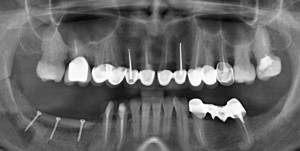

Клиническая загадка #1

Давеча мне пришлось удалить у одного пациента установленные ранее импланты одного производителя. Из одного участка зубного ряда. Одинаковым способом, а именно — специальным инструментом для удаления имплантов